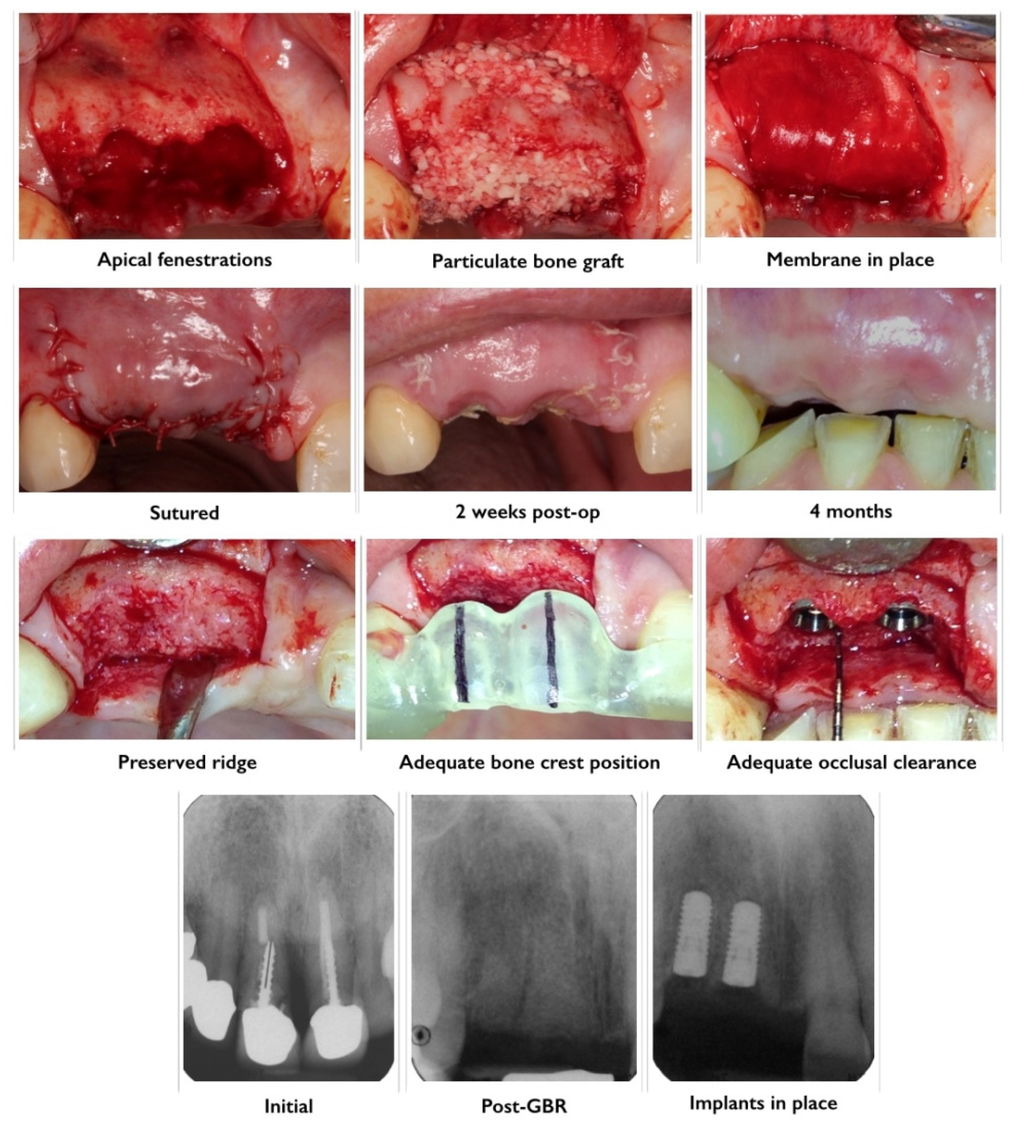

3.4. Guided Bone Regeneration

3.5. Minimally Invasive Approaches to GBR